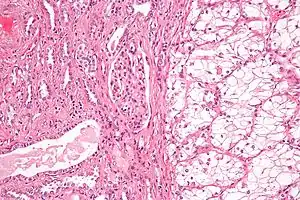

| Micrograph of the most common type of renal cell carcer (clear cell)—on right of the image; non-tumour kidney is on the left of the image. Nephrectomy specimen. H&E stain | |

Histopathology

The gross and microscopic appearance of renal cell carcinomas is highly variable. The renal cell carcinoma may present reddened areas where blood vessels have bled, and cysts containing watery fluids.[58] The body of the tumour shows large blood vessels that have walls composed of cancerous cells. Gross examination often shows a yellowish, multilobulated tumor in the renal cortex, which frequently contains zones of necrosis, haemorrhage and scarring. In a microscopic context, there are four major histologic subtypes of renal cell cancer: clear cell (conventional RCC, 75%), papillary (15%), chromophobic (5%), and collecting duct (2%). Sarcomatoid changes (morphology and patterns of IHC that mimic sarcoma, spindle cells) can be observed within any RCC subtype and are associated with more aggressive clinical course and worse prognosis. Under light microscopy, these tumour cells can exhibit papillae, tubules or nests, and are quite large, atypical, and polygonal.

Recent studies have brought attention to the close association of the type of cancerous cells to the aggressiveness of the condition. Some studies suggest that these cancerous cells accumulate glycogen and lipids, their cytoplasm appear "clear", the nuclei remain in the middle of the cells, and the cellular membrane is evident.[59] Some cells may be smaller, with eosinophilic cytoplasm, resembling normal tubular cells. The stroma is reduced, but well vascularised. The tumour compresses the surrounding parenchyma, producing a pseudocapsule.[60]

The most common cell type exhibited by renal cell carcinoma is the clear cell, which is named by the dissolving of the cells' high lipid content in the cytoplasm. The clear cells are thought to be the least likely to spread and usually respond more favourably to treatment. However, most of the tumours contain a mixture of cells. The most aggressive stage of renal cancer is believed to be the one in which the tumour is mixed, containing both clear and granular cells.[61]

The recommended histologic grading schema for RCC is the Fuhrman system (1982), which is an assessment based on the microscopic morphology of a neoplasm with haematoxylin and eosin (H&E staining). This system categorises renal cell carcinoma with grades 1, 2, 3, 4 based on nuclear characteristics. The details of the Fuhrman grading system for RCC are shown below:[62]